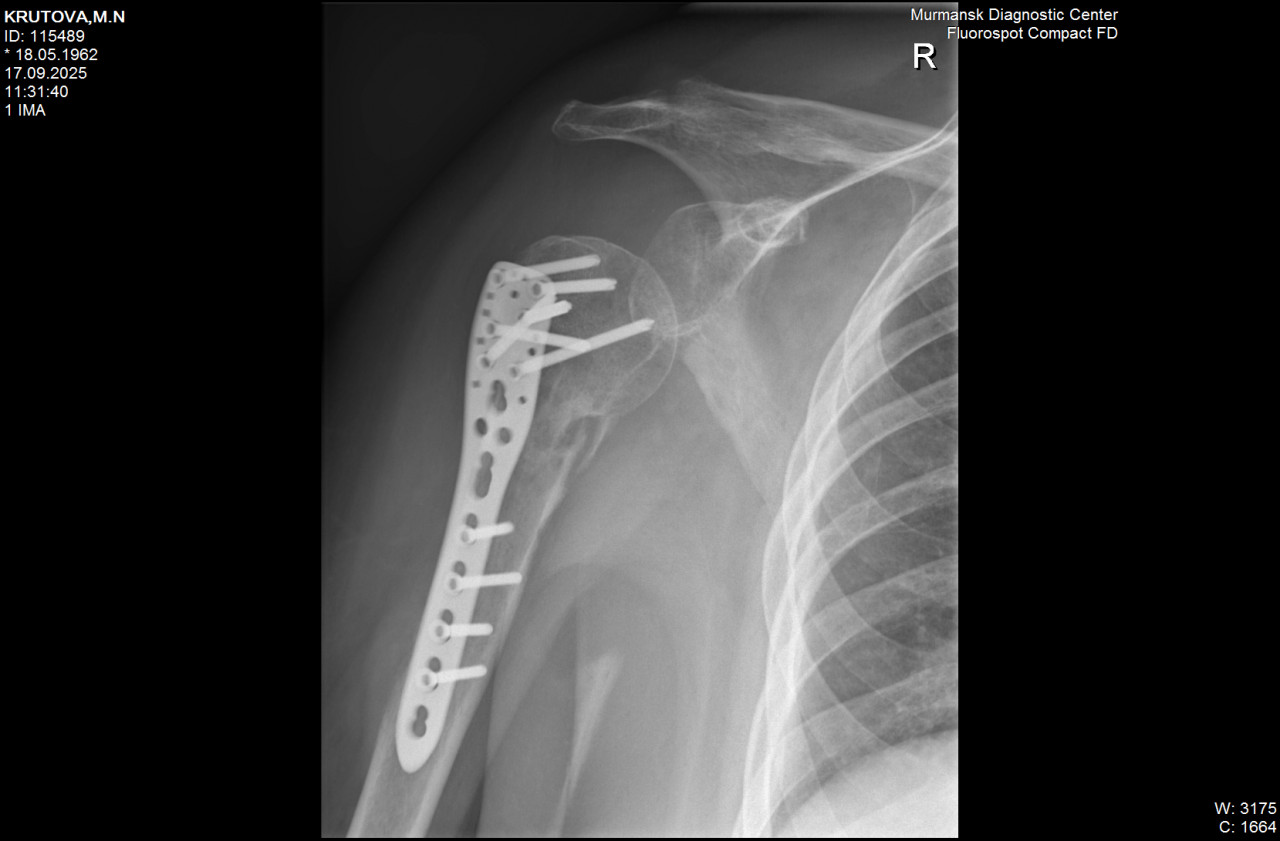

Здравствуйте! в июне перелом плеча и отрыв  большого бугорка. В июле ГИОХВ правого плечевого сустава. Сейчас в суставе бывают болевые ощущения. Рентген от 17.09.25. Насколько верно описание (делал молодой лаборант)

Здравствуйте. По рентгену видно наличие металлоконструкции, сохранность пластины и винтов, однако признаков полноценного сращения перелома пока нет, отмечается зона резорбции костной ткани, что может указывать на замедленное заживление и риск формирования ложного сустава. При диабете такие осложнения встречаются чаще, поэтому обязательно нужно очно показаться травматологу для уточнения тактики.

Здравствуйте.  По снимкам металлоконструкция стоит правильно, перелом фиксирован, но видны признаки замедленного срастания и участок перестройки костной ткани. Это может быть вариантом замедленной консолидации, не всегда остеомиелит. Важно наблюдение в динамике и дообследование (анализы, КТ/МРТ при необходимости), решение о дальнейшем лечении принимает травматолог очно.